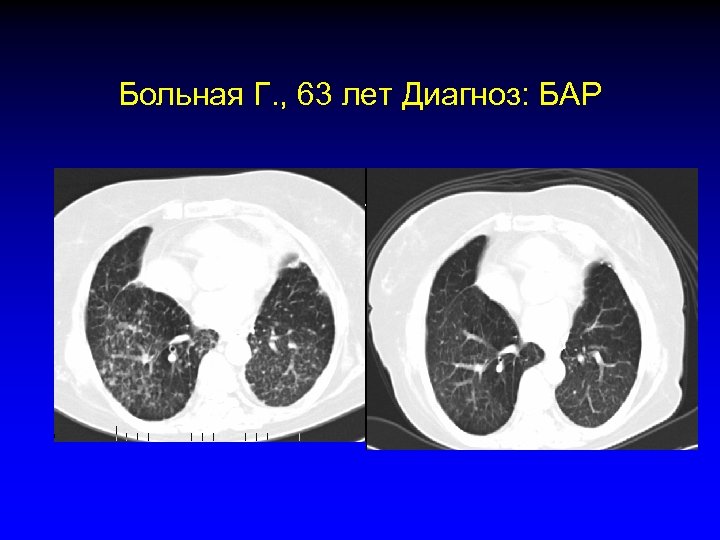

Больная Г. , 63 лет Диагноз: БАР • 2003 год. Резекция нижней доли левого легкого по поводу узловой формы БАР • 2004 год. Рецидив заболевания диффузная форма БАР, ПХТ 1 -я линия (платина) • 2005 январь. Прогрессия заболевания, 2 -я линия ХТ (таксол) • 2005 май. Прогрессия заболевания, 3 -я линия терапии (иресса) • 2005 июль. Частичный ответ • 2005 сентябрь. Полный ответ

Больная Г. , 63 лет Диагноз: БАР